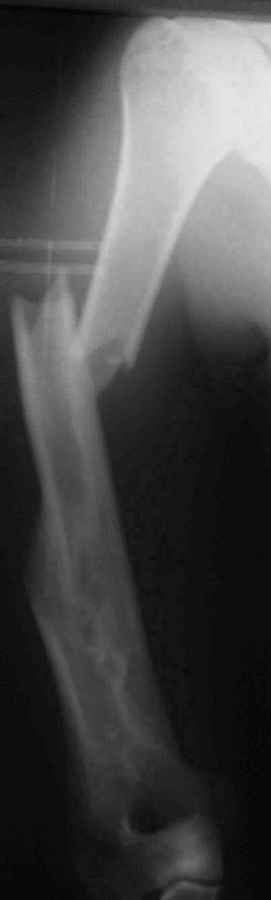

Несмотря на то, что всё это "хорошо компенсируется функционально" В приложенном файле - случай ложного сустава плеча, сформировавшегося после консервативного лечения перелома.(И почему эти оставшиеся 10% так часто попадают ко мне!). Пациент 51 года, соматически здоровый некурящий житель московских окраин ("спальный" район), 4 года назад лечился в одной из наших клинических больниц. Его заверили в том, что переломы плеча срастаются всегда, а уж если у него нет консолидации, то оперировать тем паче нельзя ввиду жуткой биологии. И только на 5ом году болезни он решил узнать второе мнение. Я не был оригинален - аутоспонгиоза, хронос плюс блокированная пластина (см вложенный файл). Ещё раз подчеркну, что я не отрицаю других путей в лечении этого ложного сустава. Но я выбрал данный. Удачи. Киев - Москва. Андрей Волна